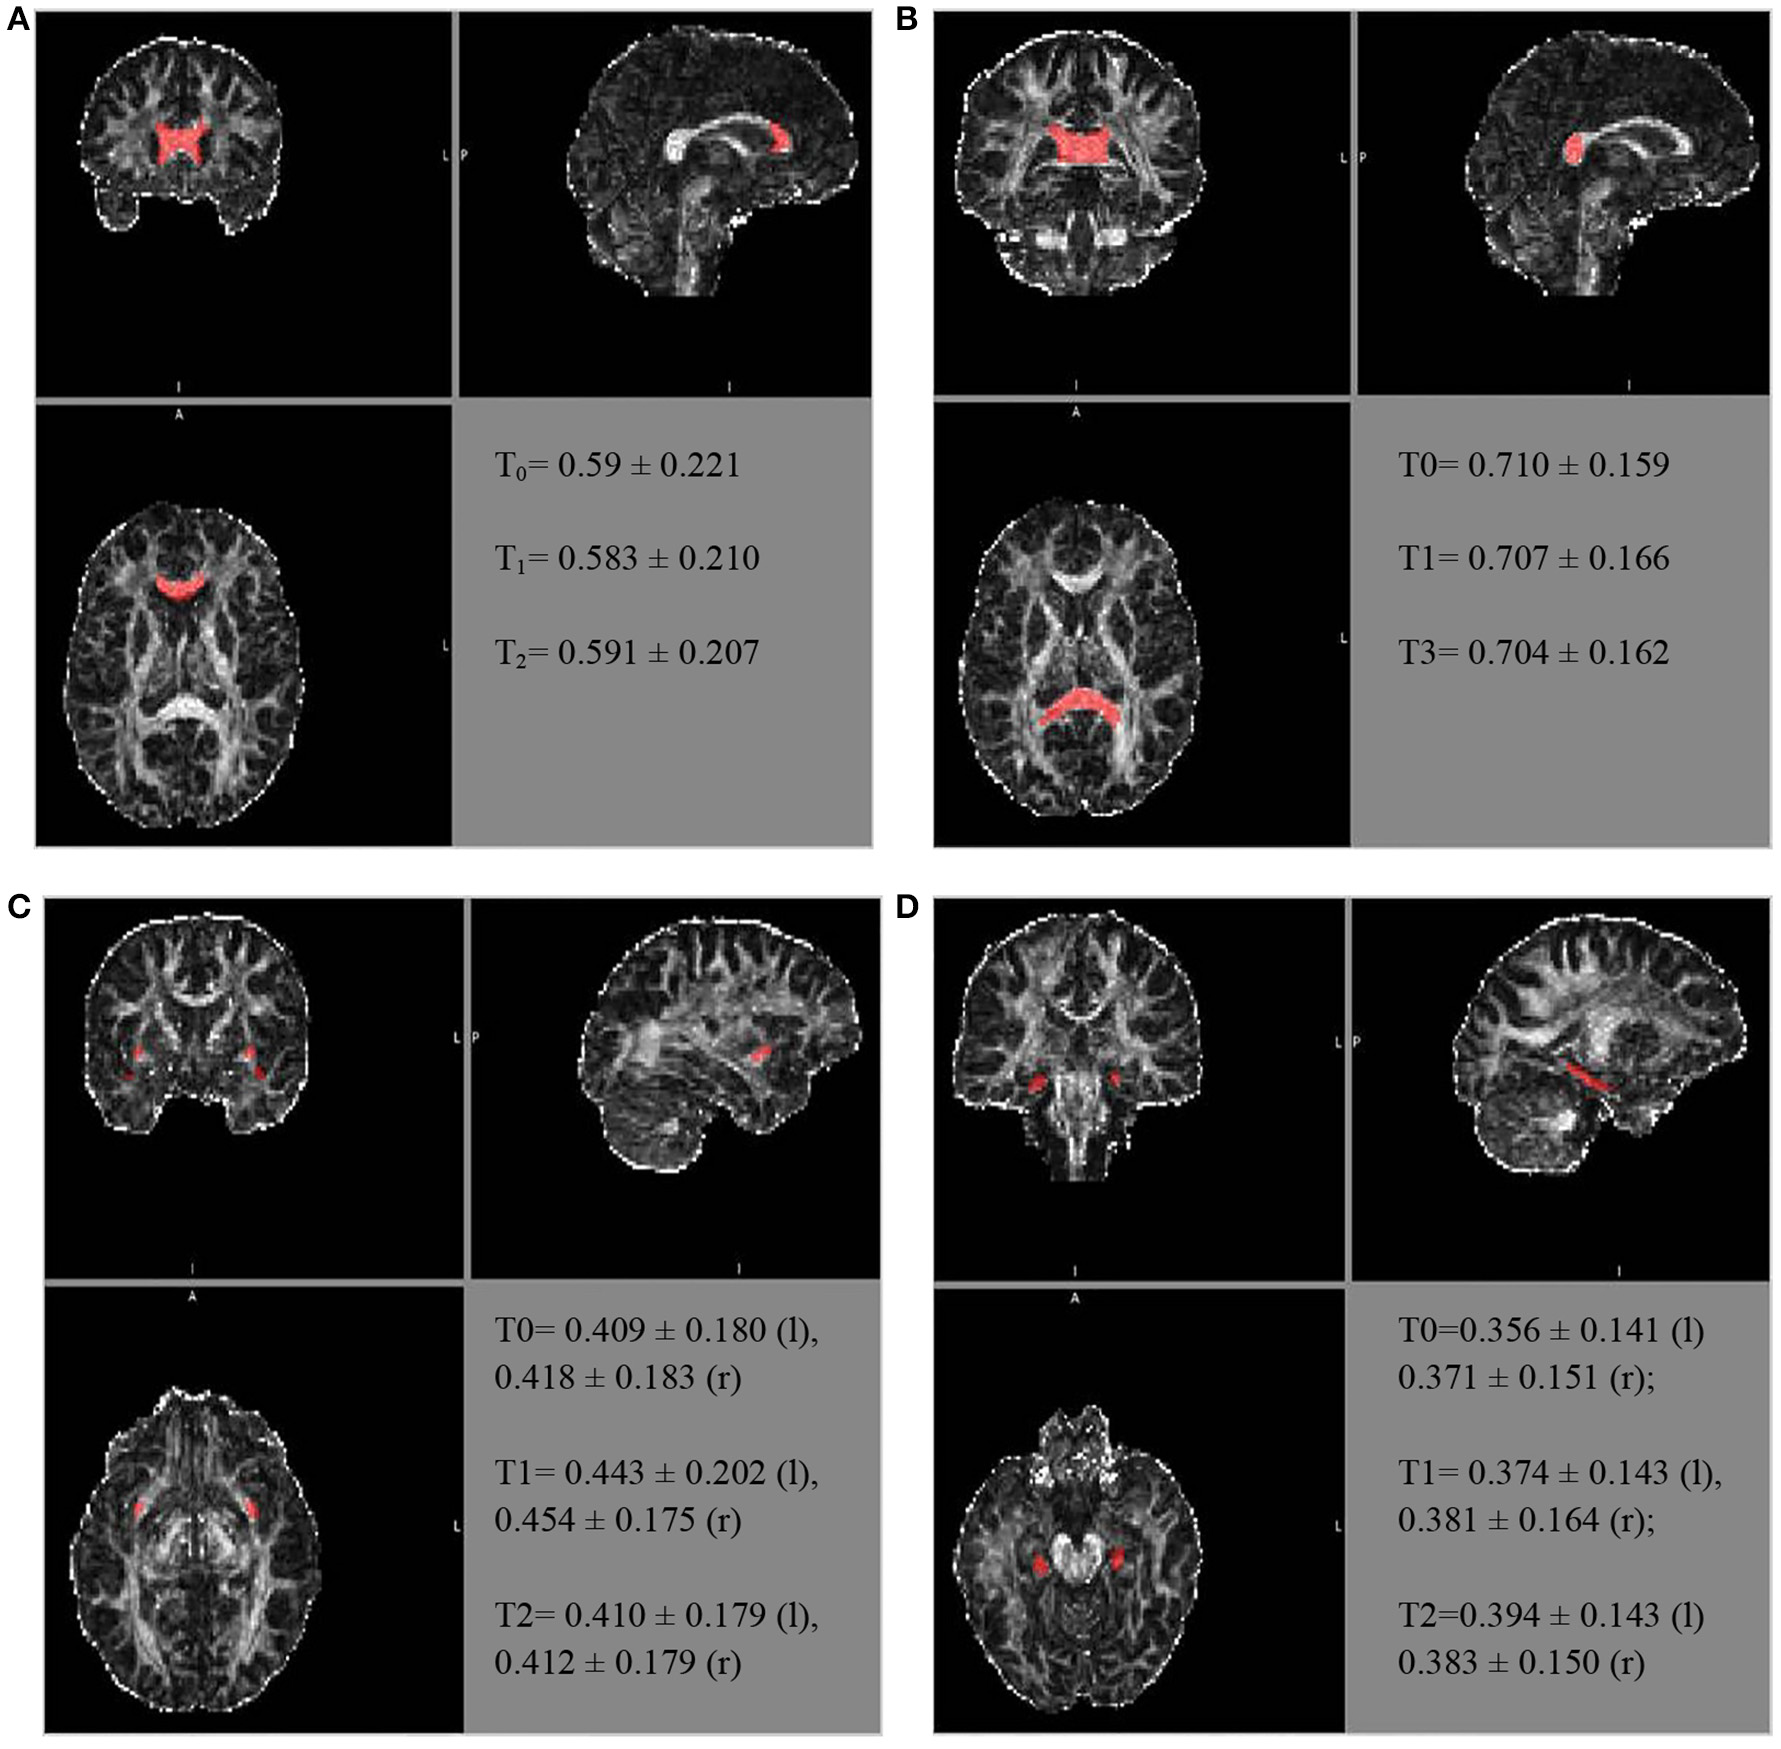

Similarly, further mean FA estimates were performed for the hippocampal cingulate fascicule and the splenium of the CC, bilateral, using the JHU-ICBM-labels-1 mm. The FA estimates were also performed for the bilateral uncinate fascicule from the WM atlas JHU-ICBM-tracts-prob-1 mm, which has better fascicule representation, following the steps described above. Figure 2 presents similar FA values for the different ROIs during the follow-up. The mean FA values of the CC's splenium was 0.710 ± 0.159 before treatment, 0.707 ± 0.166 for T1, and 0.704 ± 0.162 for T2. The mean FA values for the hippocampal cingulate fascicule for T0, T1, and T2 were: 0.356 ± 0.141 (l:left) 0.371 ± 0.151 (r:right); 0.374 ± 0.143 (l), 0.381 ± 0.164 (r); and 0.394 ± 0.143 (l) 0.383 ± 0.150 (r), respectively. For the uncinate fascicule, the results of mean FA values for T0, T1, and T2 were: 0.409 ± 0.180 (l), 0.418 ± 0.183 (r); 0.443 ± 0.202 (l), 0.454 ± 0.175 (r); and 0.410 ± 0.179 (l), 0.412±0.179 (r), respectively.

Figure 2. The longitudinal FA variation for different regions of interest. The atlas showing the locations for the (A) genu of the CC, (B) splenium of the CC, (C) uncinate fascicule right r/l, and (D) cingulate hippocampal fascicule r/l.

The FA of the genu of the CC, using the JHU tract probe in MATLAB, presented small variations between T0, T1, and T2 (T0 = 0.523473; T1 = 0.507267; T3 = 0.491564), toward FA reduction. After adjusting by the JHU tract probe FSL, the analyses were similar among the periods of assessment (T0 = 0.504 ± 0.216; T1 = 0.493 ± 0.205; T2 = 0.502 ± 0.2066), as well as after the JHU/Labels, 1 mm (T0 = 0.59 ± 0.221; T1 = 0.583 ± 0.210; T2 = 0.591 ± 0.207), without a reduction trend (Figure 2).